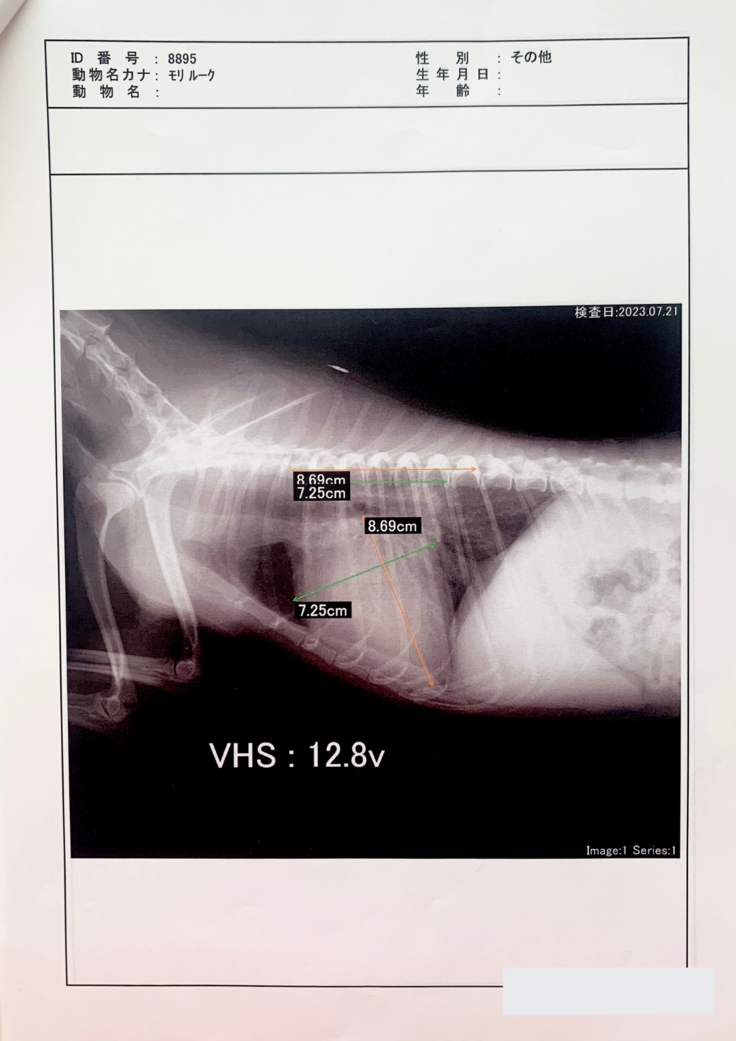

その後、また呼吸が苦しそうで一度酸素室に2日ほど入院しました。そして、僧帽弁閉鎖不全症手術の名医がいる病院を紹介され、そこで検査を受けてきた次第(7/21)です。

重症と診断され、手術は8月中に受けられる見込みとなりました。

手術を行う病院での検査(7/21)以降、自宅で安静にしていますが、心臓が肥大していることから出る咳が頻発すること、僧帽弁閉鎖不全症後期である泡のような嘔吐の症状があるため、通院/検査をしながら日々を送っております。